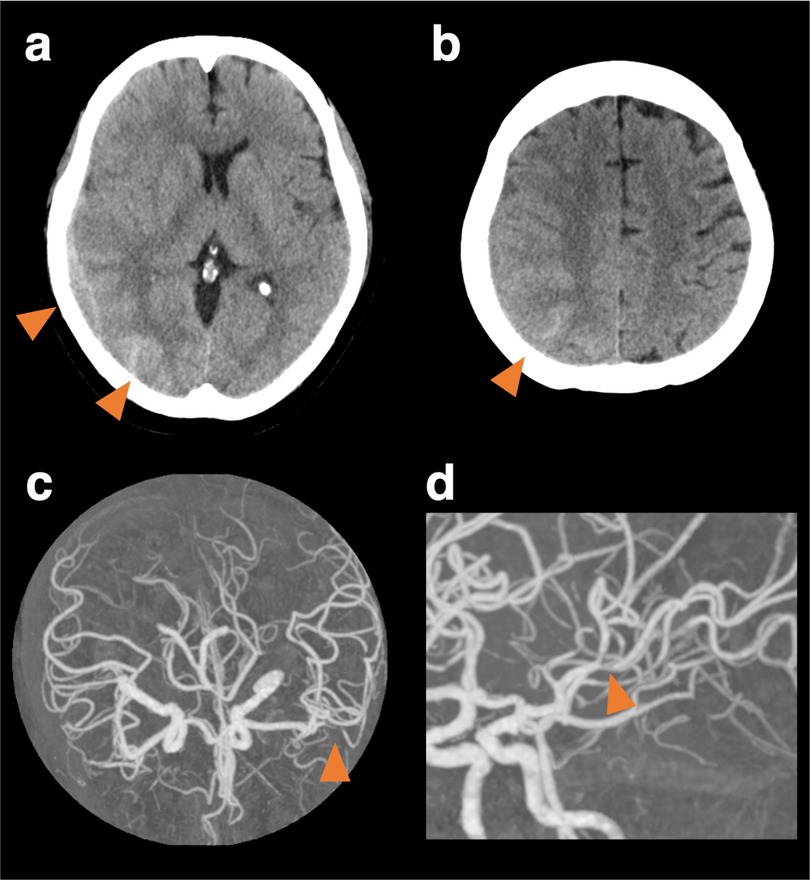

A 59-year-old woman with cardiomyopathy due to Duchenne muscular dystrophy underwent cardiac transplantation. Her pre-transplant history included muscular dystrophy-related weakness but no history of hypertension, migraine, or other significant cardiovascular comorbidities. Her perioperative immunosuppression regimen consisted of tacrolimus, mycophenolate mofetil, and prednisolone. She had been taking aspirin for donor-transmitted coronary atherosclerosis. Her postoperative course was complicated by labile hypertension, with systolic pressures ranging from 140 to 180 mmHg. On day nine, she developed a headache. Neurological examination revealed left lower quadrantanopia. A head Computed Tomography (CT) scan showed a subdural hematoma with a maximum thickness of 1 cm, along with a subcortical and convexity subarachnoid hemorrhage in the right parieto-occipital lobe (Figures 1a,b). CT angiography revealed stenosis confined to the left middle cerebral artery, though it was unclear whether this represented vasospasm or mere stenosis (Figures 1c,d). MR imaging was not immediately available due to the presence of transplant-related devices. Discontinuation of aspirin did not prevent the development of left hemineglect on the 10th day. After the transplant-related devices were removed, cranial MR images on the 10th day revealed a watershed infarct in the right parietal lobe (Figures 2a,b), and MR angiography demonstrated diffuse, multifocal moderate vasospasms affecting the bilateral anterior, middle, and posterior cerebral arteries (Figure 2c). She was diagnosed with RCVS. Management included immediate withdrawal of tacrolimus and initiation of oral verapamil. Following the identification of the watershed infarct, an antiplatelet agent was considered for secondary stroke prevention. Prasugrel was chosen over other P2Y12 inhibitors because its antiplatelet effect is not influenced by CYP2C19 loss-of-function variants, which are prevalent in Asian populations (5). This regimen led to an improvement in her neurologic symptoms within 24 h, and follow-up MR angiography on day 18 showed improvement in the vasospasm (Figure 2d). Her immunosuppressive regimen was adjusted to a combination of prednisolone, everolimus, and mycophenolate mofetil, and then gradually tapered. She was discharged home on day 49. At a 6-month follow-up visit, she remained neurologically stable with a persistent, isolated left lower quadrantanopia but was independent in her activities of daily living (modified Rankin Scale score of 1). Follow-up cranial magnetic resonance imaging at 6 months revealed no new infarction or hemorrhage and no recurrence of vasospasm.

Figure 1

Cranial computed tomography and computed tomography angiography at the onset. Cranial computed tomography (CT) shows subcortical hemorrhage in the right posterior lobe, subdural, and convexity subarachnoid hemorrhage (a, b). CT angiography shows vasoconstriction limited to the left middle cerebral artery, though it was unclear whether it was a vasospasm or mere stenosis (c, d).